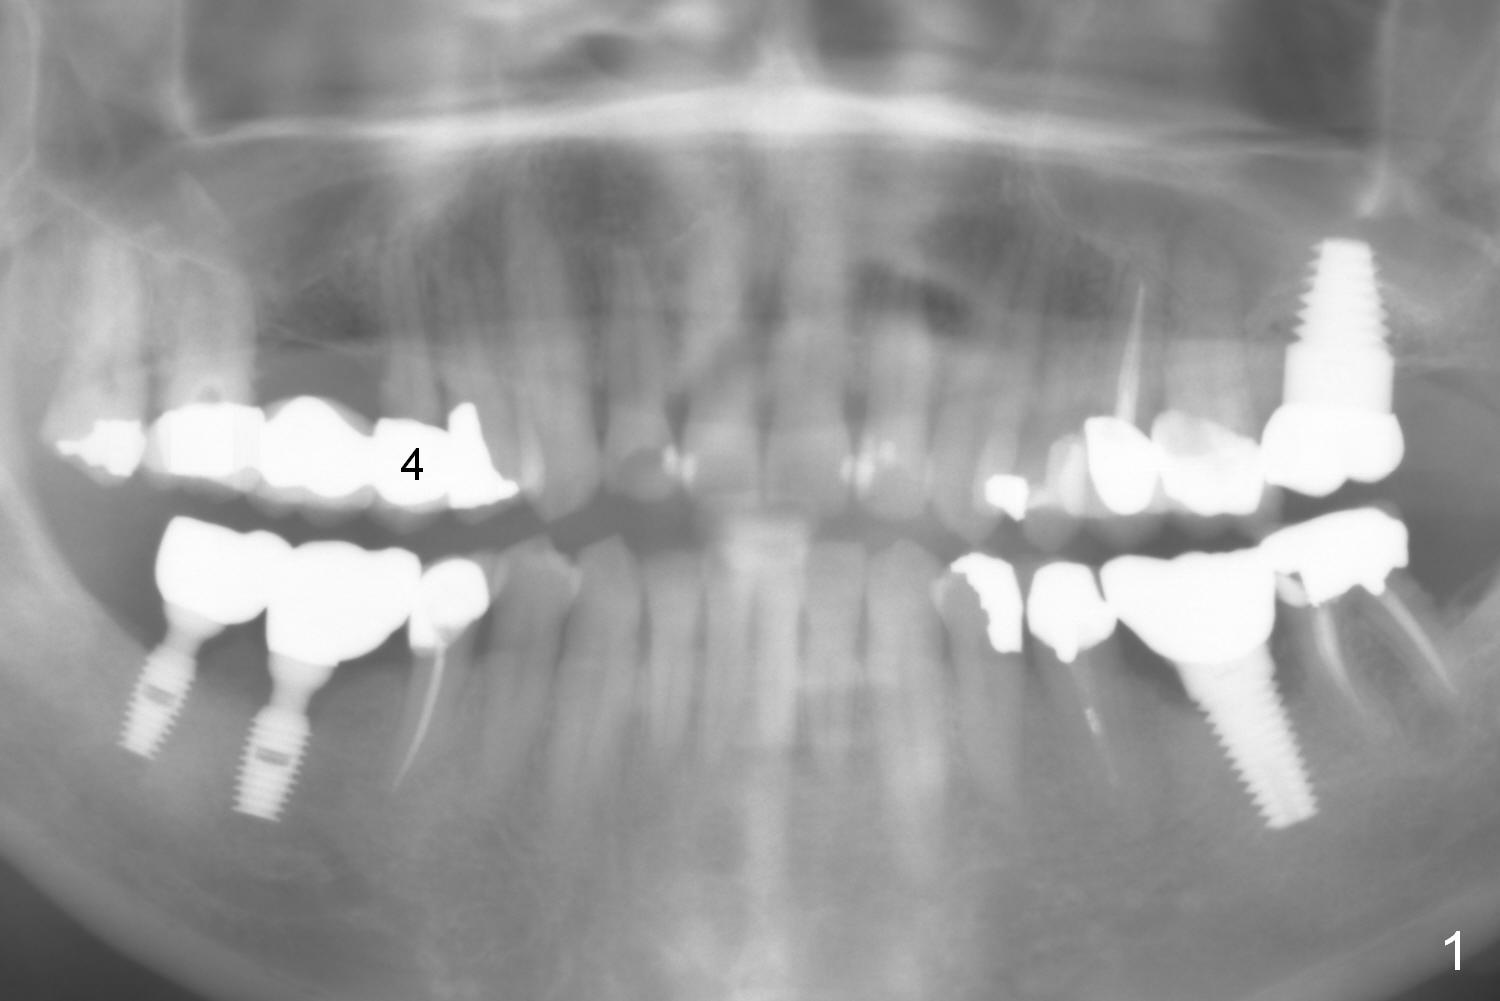

A 63-year-old man complains of loose bridge in the upper right quadrant. There is open margin at #4 (Fig.1). After sectioning between #2 and 3 without anesthesia, explore the tooth/abutment of #4 for caries. Build up or Cavit will be placed for splinted provisional with implant at #3. Use Magic Split for access and initial bone expansion, followed by Magic Expanders until 4.3 mm one. Bone density is 100-500 units. The depth starts with 7 mm and finishes with 9 mm or more from gingival margin (Fig.2). CBCT coronal section shows the bone width 8.6 mm (Fig.3). Place a 4.5x9 mm dummy implant at the gingival level for depth determination. Use a definitive implant 1-2 sizes larger (Fig.4,5). Draw blood for PRF. Also prepare Magic Lift Kit and DIO one.